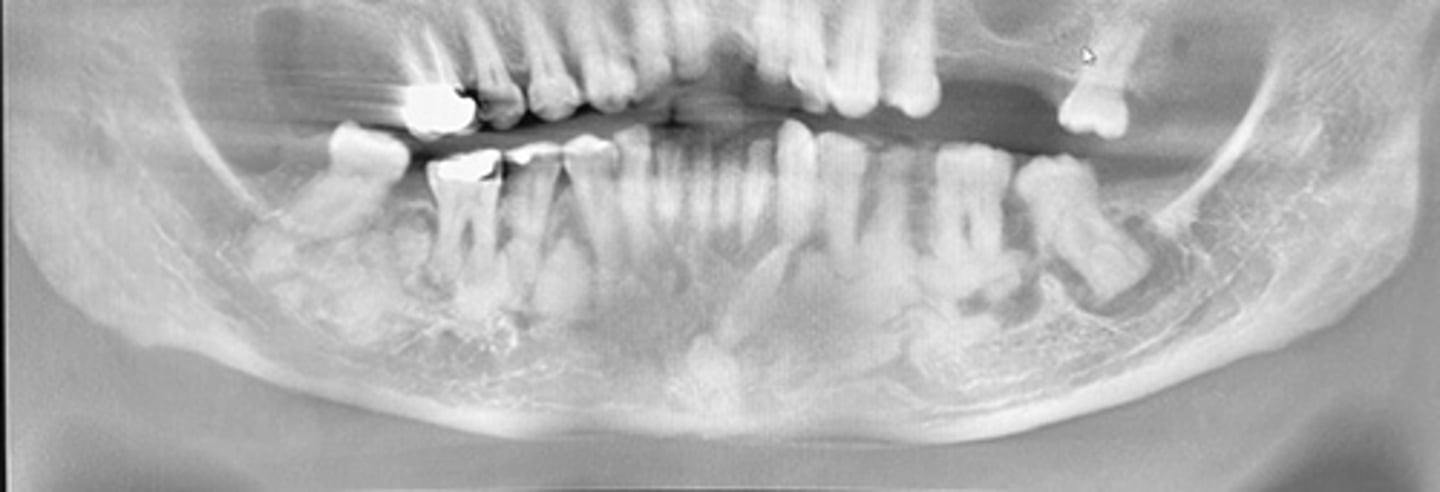

Extraoral imaging examination

inspection used to examine large areas of the skull or jaws

what is this?

what is this radiolucent area in the image?